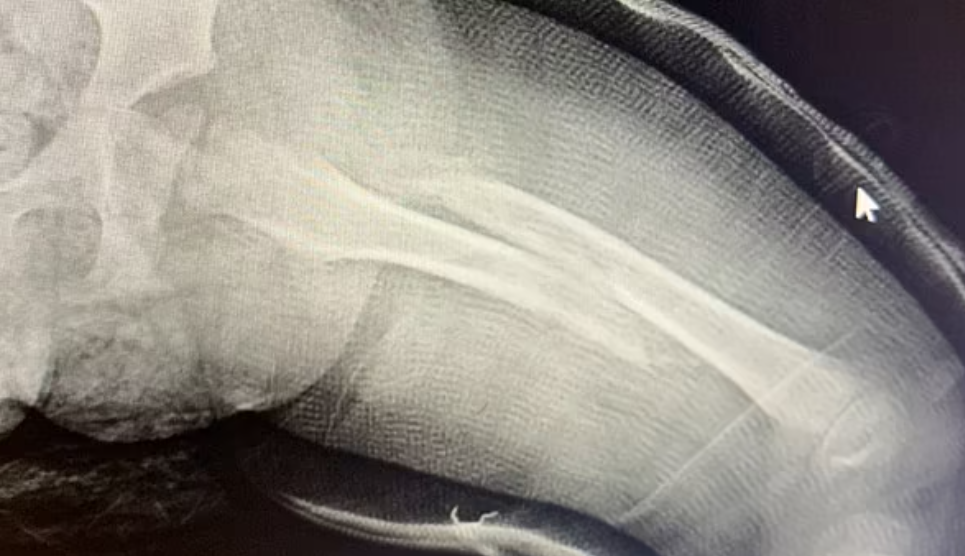

因为症状非常严重,这名男童不得不接受手位保育人员是32岁的Elicia Mil

新开始学习走路。 他的父亲透露说:“后,男孩的父亲来接他回家,却发现儿子一直